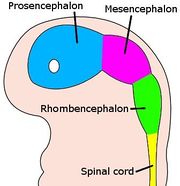

| 28. 5. 2010, 08:56 | Mozek embrya 4 tydny.jpg (soubor) |  | 20 kB | Webmaster | 1 | |